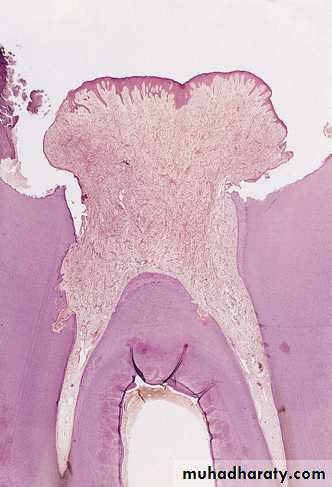

Acute pulpitis. Low-power view showing occlusal caries penetrating to the pulp through a layer of reactionary dentine.There is a focus of acute inflammatory cells beneath the carious exposure in the pulp horn.

Acute pulpitis:

Acute pulpitis. Beneath the carious exposure (top right).a dense inflammatory infiltrate is accumulating. More deeply, the pulp is hyperaemic, with dilated blood vessels.

Acute pulpitis: Infection seen as, (dark lines of bacteria along tubules) & has penetrated a thin layer of reactionary dentine on the roof of the pulp chamber causing inflammation throughout the pulp and pus to form in the pulp horn.Acute pulpitis: